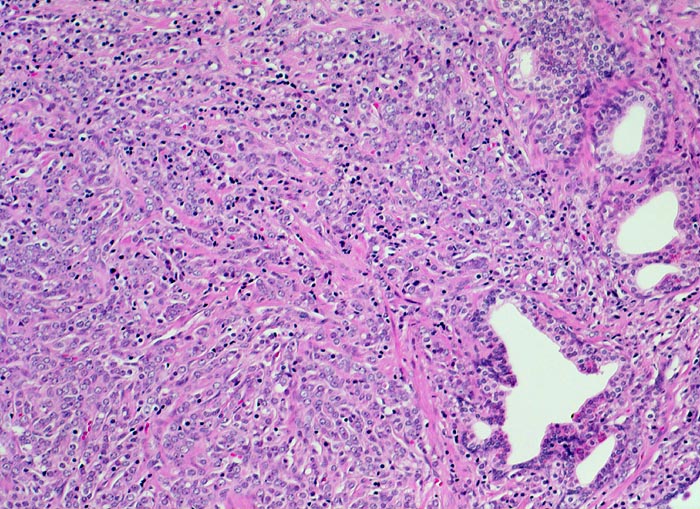

Morphologische Merkmale:

• Normale Prostatadrüsen mit grossen Lumina angeordnet in Läppchen. Das Epithel bildet Falten und besteht aus einer inneren hochprismatischen sekretorischen Zellschicht und einer äusseren Schicht flacher Myoepithelien.

• Herde kleiner Karzinomdrüsen ohne Basalzellschicht.

• Fehlende lobuläre Anordnung der Karzinomdrüsen.

• Konfluierende Drüsen bilden kribriforme Muster.

• Karzinomzellen mit stark erhöhter Kern-Zytoplasmarelation und hyperchromatischen Zellkernen mit grossen eosinophilen Nukleolen.

• Wenig differenzierte Karzinomanteile ohne erkennbare Drüsenbildung.

• Perineuralscheideninvasion.

• Links oben im Präparat finden sich Anteile der Samenblase mit polymorphem Epithel und gelben Lipofuszinpigmenteinlagerungen.

• Unterhalb der Samenblase sind von flachem Endothel ausgekleidete Lymphgefässe mit Karzinominfiltraten erkennbar (Lymphangiosis carcinomatosa).

• Der mit schwarzer Tusche markierte Resektionsrand in der unteren Hälfte des Präparates ist tumorfrei.